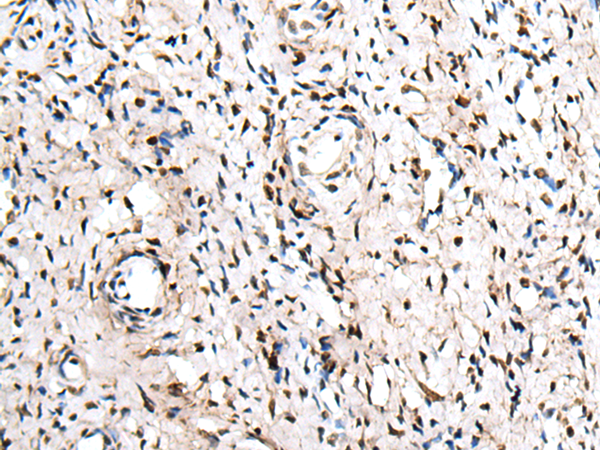

IHC positive control:

IHC Recommend dilution:

25-100